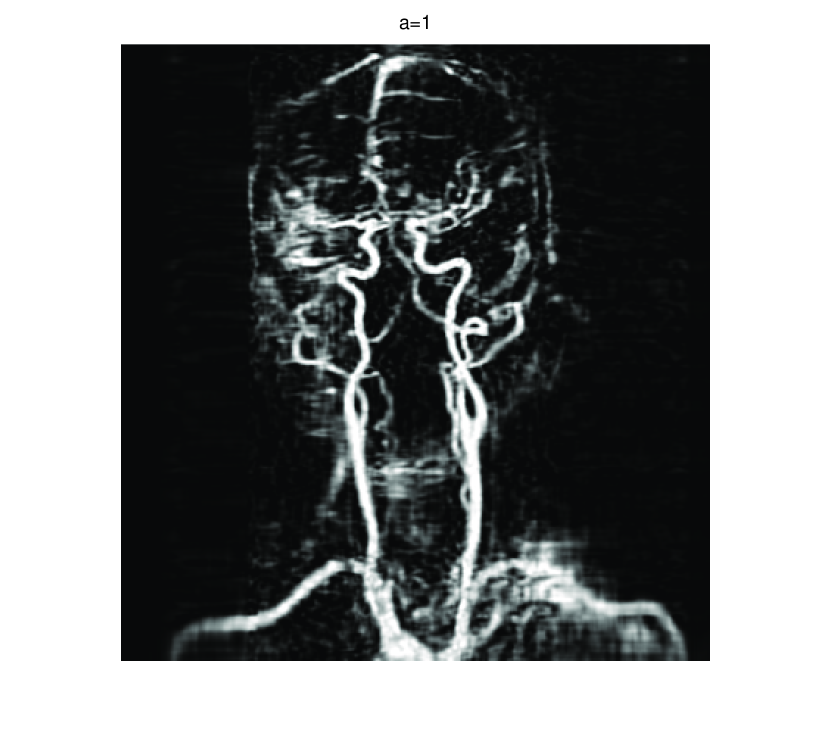

In this section, we first present numerical results of ISVTA for matrix completion problems, and then compare it with some state-of-art methods (singular value thresholding algorithm (SVTA) and singular value projection algorithm (SVPA) respectively proposed in [11] and [31]) for image inpainting problems. Numerical experiments on matrix completion problems show that our method performs powerful in finding a low-rank matrix and the numerical experiments about image inpainting problems show that our algorithm has better performances than SVTA and SVPA. Among all of the experiments, differing from the Scheme 2, we set , and

5.2 Image inpainting

In this subsection, we demonstrate performances of ISVTA on image inpainting problems. The ISVTA is tested on some medical grace images ( Brain angiography image (BAI), Hand angiography image (HAI) and Intracranial venous image (IVI)). We use the SVD to obtain their approximated low-rank images with rank , respectively. Numerical results of ISVTA for theses low-rank image inpainting problems are reported in Table 5, 6, 7, 8.

Table 5, 6 show that ISVTA performs powerful in finding a low-rank matrix on image inpainting problems. Indeed, we could get an exact low-rank image by the ISVTA by choosing proper . Moreover, it is necessary to point out that our method does not work well for all , and we can find that is not a good strategy for the low-rank IVI either or . The numerical results of ISVT, SVTA and SVPA compared in Table 5, 6, 7, 8, 9, 10 under same circumstance show that the ISVT algorithm performs far more better than ISTA and SVPA on image inpainting problems for some proper .